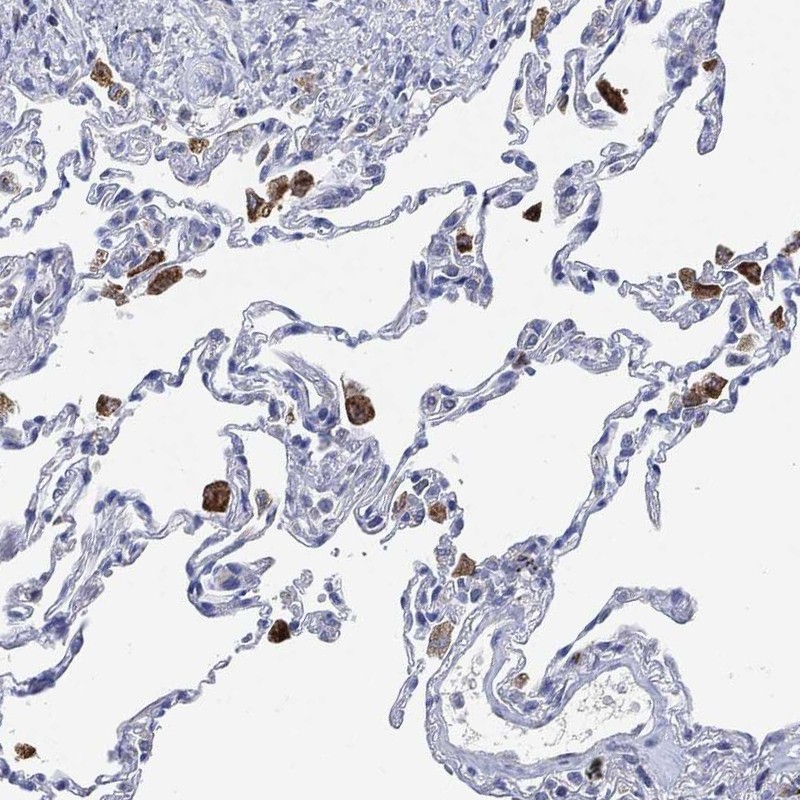

Immunohistochemical staining of human lung shows cytoplasmic positivity in macrophages.